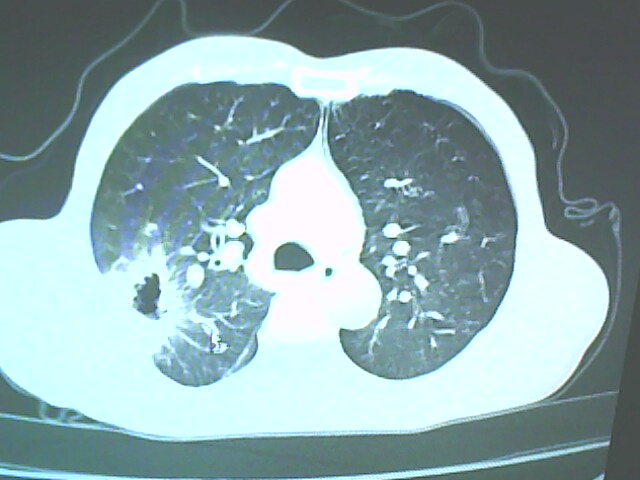

患者,男,66岁,以咳嗽、咳痰伴胸痛来就诊。

胸片提示右上肺占位病变。请各位老师看看ct。

考虑癌性空洞可能性大,空洞内壁不规则,病灶周围模糊,分叶、有毛刺

空洞内壁不规则,病灶周围模糊,分叶、毛刺呈日光放射状,突然截断,支持考虑癌性空洞

考虑右肺上叶后段周围型肺癌并癌性空洞形成。

考虑癌性空洞可能性大,内壁不规则,洞壁薄厚不均呈结节状突起,边缘模糊,分叶,毛刺

右上肺后段肺癌:

典型癌性空洞(偏心性,壁厚薄不均,内壁不光整),周围毛刺较僵硬,且有刺突征和血管聚集征